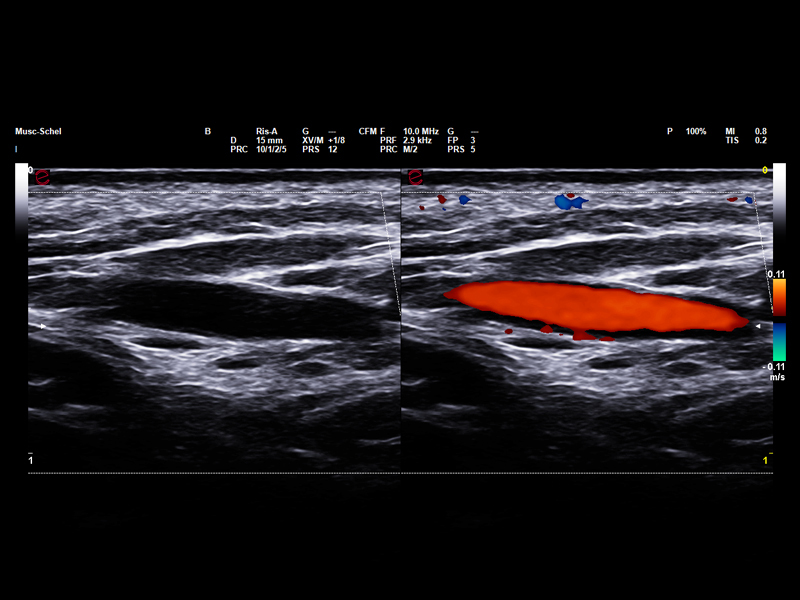

Microvascular insights in sports medicine

In sports medicine, Power Doppler allows for accurate evaluation of inflammation and monitoring of healing, particularly in soft tissue and overuse injuries. Esaote’s highly sensitive Power Doppler technology has been designed to optimize visualization of lowflow signals in small, superficial vessels, which are typical of early or low-grade inflammatory processes, thereby supporting accurate diagnoses and tailored follow-up. With the addition of microV technology, Esaote is pushing the boundaries of microvascular imaging, enabling early detection and detailed characterization of musculoskeletal injuries, which is vital for their effective management and for developing faster return-to-play strategies.